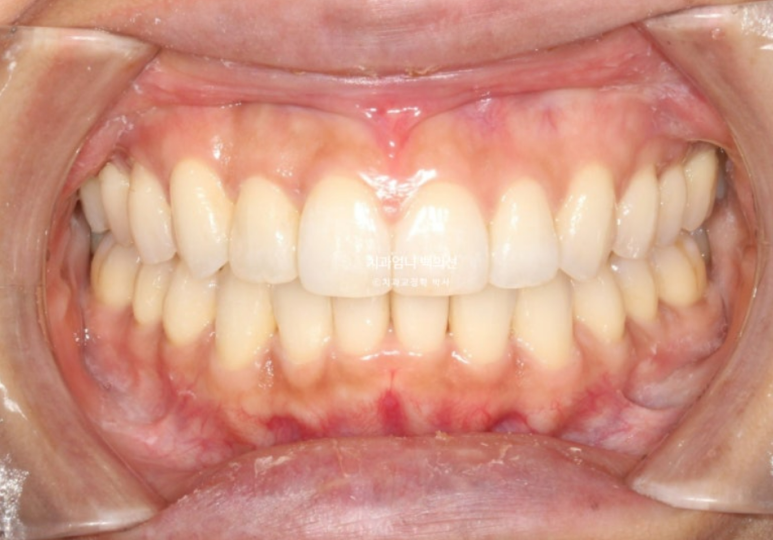

25년 2월에서 4월까지 3달간 두번째 추가장치를 모두 끼고 25년 4월에 드디어 치료를 마무리 했습니다.

총 치료기간은 1년 6개월 소요되었고 재제작은 총 2회입니다.

중심선은 잘 맞고 치축이 미세하게 기울어져 보이던 앞니도 개선이 되었습니다

교정치료의 기본은 교합입니다 교합이 좋지 않으면 교정치료를 마무리 짓지 않습니다.

가지런해진 배열과 유지장치 모습입니다.

위 아래 앞니 중심선은 정확히 매치가 됩니다.

덧니는 잘 배열되었습니다.

깔끔하고 적절한 스마일라인

덧니쪽으로 쏠려있던 앞니 중심선이 코와 인중이 맞게 되었습니다.

앞니각도도 적절합니다.

원래 예뻤던 입매는 잘 유지가 되었습니다.

치근흡수는 없고 치근평행도는 좋습니다.

인비절라인 교정은 철사 브라켓 교정에 비해서 치아에 가해지는 힘이 약한 만큼 경험상 오래 걸리는 교정이여도 전반적으로 치근흡수는 거의 없습니다.

1년 6개월간 변화로 입술이 좀더 편하게 다물리게 되었습니다.